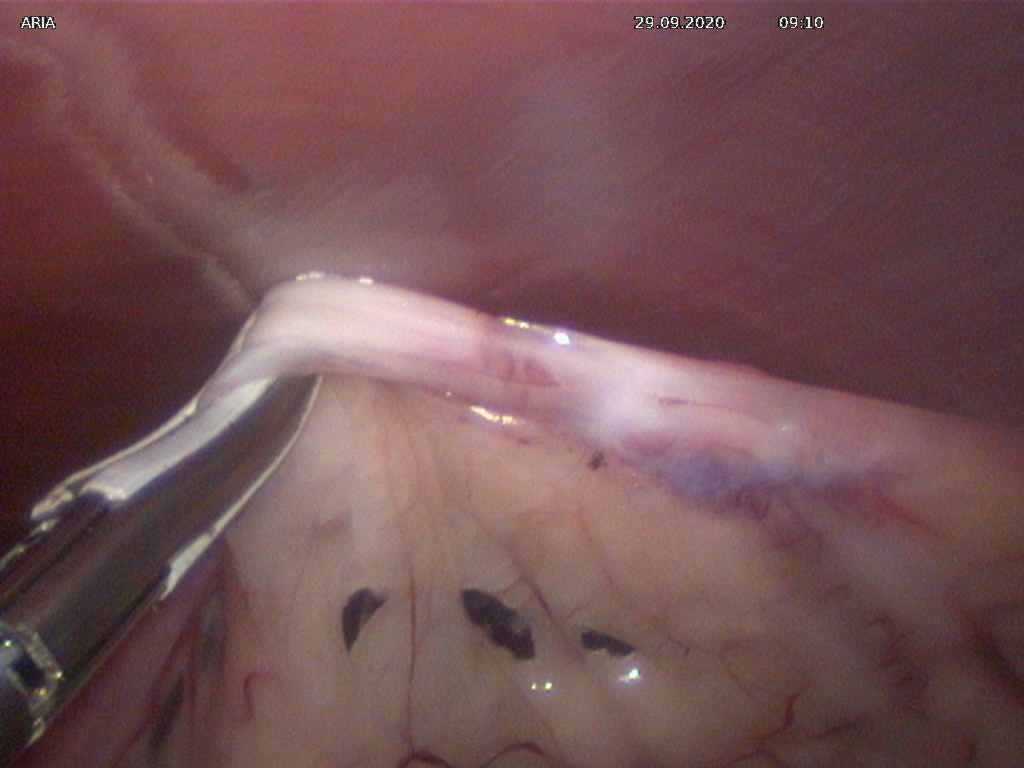

L’intervento ha riguardato l’asportazione delle ovaie di una canina di media taglia in laparoscopia. La […]